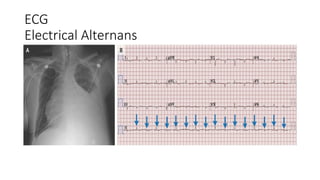

ECG

Electrical Alternans

Investigation • Trans OesophagealEchocardiiography: Gold standard for Dx. Presence of 1 cm pericardial separation • TTE: more unreliable • Cxr: widened mediastinum with globular heart shadow, difficult to interpret • ECG : pulsus alternans